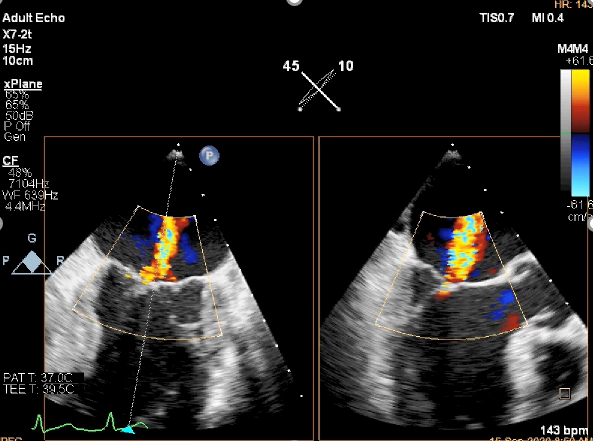

TEE短轴脱垂区域显示(P2、P3区大范围脱垂)

TEE短轴脱垂区域显示(color,血流来源于P2、P3区)

患者麻醉方式同样采取全麻,建立静脉通路后,穿刺右侧股静脉后,预埋ProGlide缝合器后,送导管至房间隔部位,成功穿刺房间隔后进入左房,调整导管角度,顺利到达二尖瓣目标位置,后在X线及食道超声联合辅助下,宋光远教授使用2枚XTR二尖瓣夹,在精确定位后,准确夹合二尖瓣A2-P2以及A3-P3区域,患者收缩压即刻上升30mmHg,左心房收缩压由62mmHg下降至28mmHg,术中测反流面积明显减少,肺静脉多普勒波形由反向恢复正常。手术顺利结束,术后患者即刻苏醒,安返病房。

二尖瓣联合部切面引导第一枚XTR夹子转向病变区域并逐渐进入左室

第一枚XTR夹子到达病变区域捕获瓣叶并逐渐夹闭

XTR夹子释放,残余部分返流